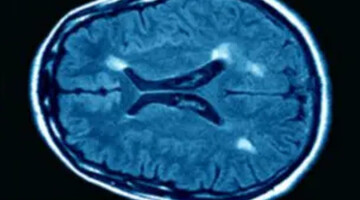

شیوع دو برابری اماس در زنان

اماس یکی از مهمترین علل ناتوانی جسمی در جوانان است که نرخ ابتلا به آن در زنان، دو برابر مردان گزارش شده است. پزشکان نسبت به ضرورت آگاهی عمومی و تشخیص زودهنگام هشدار میدهند.